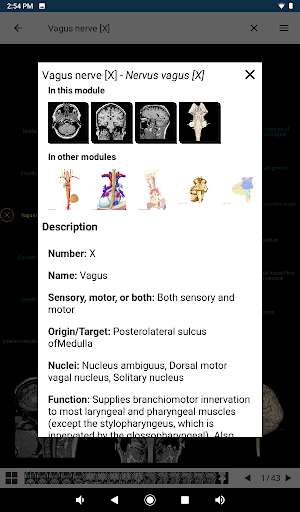

* تحسين عرض التفاصيل للأجزاء التشريحية لتسهيل التعرف عليها في صور الوحدات الحالية والوحدات الأخرى.

* تحسين رؤية تعريفات الأجزاء التشريحية

* تصفح بين الأجزاء التشريحية باستخدام روابط الوصف